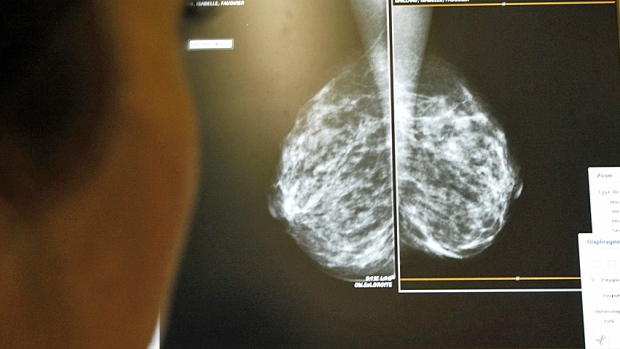

【加拿大头条(ID:canadanews)乐球球报道】根据美国食品药监局(U.S. Food and Drug Administration,简称FDA)的数据,有9起十分罕见的癌症 死亡病例与隆胸有关。

FDA得到了世界卫生组织的同意,停止这种于多年前就开始实行的隆胸手术,因为会导致淋巴瘤。

FDA强调,癌症不一定就只是乳腺癌,而是由隆胸引起的淋巴瘤。这种类型的癌症,病情发展缓慢,大多数患者都可以通过手术移除植入体。